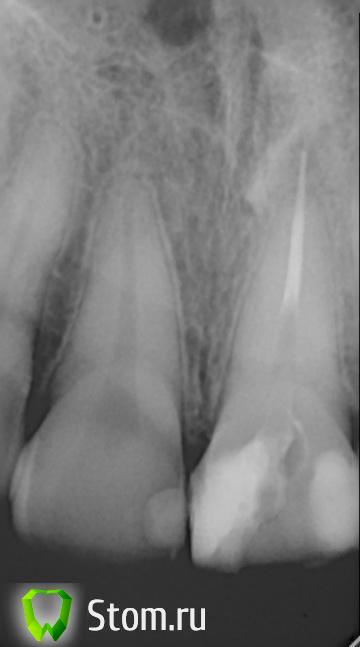

sunnyyy Опубликовано 9 февраля, 2012 Поделиться Опубликовано 9 февраля, 2012 В январе залечила (перелечила) передний зуб. Были пролечены каналы и поставлен штифт. После лечения зуб болел,но я посчитала в пределах нормы, т.к пульпит. Прошла неделя,стало полегче,но все равно болит если по нему даже ногтем постучать, он ощущается на морозе, при двежении губ, перепаде давления. Сейчас прошел уже месяц.Сделала снимок. Один стоматолог говорит, что штифт вышел за грани канала и дает боль,нужна только резекция, иначе начнуться образовываться гранулемы и кисты. Другой говорит, что "боли скорее всего не из-за выведенного материала (он инертный и болей не вызывает обычно)"...может и удасться решить проблему консервативно.Подскажите в чем проблема? Очень бы хотелось чтоб проблему можно было решить консервативно.Врач у которого лечила-в отпуске и + я в другом городе Ссылка на комментарий

Afffinity Опубликовано 9 февраля, 2012 Поделиться Опубликовано 9 февраля, 2012 Гуттаперчевый штифт прилично выведен за верхушку, оттого и боли. Для начала попробовать достать его через канал, если не получиться то РВК вам в помощь Ссылка на комментарий

sunnyyy Опубликовано 14 августа, 2012 Автор Поделиться Опубликовано 14 августа, 2012 Добрый день! Продолжение истории.... Штифт был удален, полностью "намыт" канал. вторая пломба не неперелечивалась.На 2 недели был поставлен каласепт, через сутки боль ушла, я выдохнула, но за 2 дня до приема началитсь неприятные ощущения в зубе. с середины зуба боль при постукивании по нему (даже ногтем), особенно после сна заметны ощущения. но все равно канал был запломбирован. По снимкам, материал уже не выходит за верхушку.Пришла к врачу,через несколько месяцев, говорю, болит, она гооврит даже не знаю чем вам помочь. Пошла к другому врачу (к которому ушла после этой ситуации). Сделали несколько контрольных снимком, врач говорит, что залечено идеально, даже не придраться. сейчас хожу на лазер. Оущения уходят, но не полностью.В чем может быть проблема?Уже пугает 3-е перелечивание этого зуба. Если перелечивать, то нужно будет снимать обе пломбы? Ссылка на комментарий

sunnyyy Опубликовано 16 августа, 2012 Автор Поделиться Опубликовано 16 августа, 2012 http://s006.radikal.ru/i215/1208/ad/969aa29b4faat.jpg Ссылка на комментарий